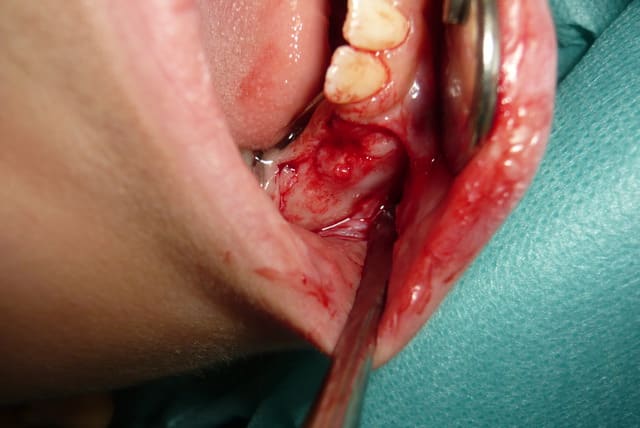

-lambeau vestibulaire à décharge trapézoîdale, à distance du foramen mentonier.

-décollement individualisation du foramen et protection lors de l'écartement

-morcellement simple de la dent et extraction..

-cone beam réalisé avant l'acte permettant de visualiser le foramen situé ici entre germe de 4 et 5 donc inévitable lors de la chirurgie.

- choix d'un lambeau avec décharges et à distance du foramen permettant de l'individualiser avec un décollement prudent. Puis protection idéalement par un écarteur non compressif :

séparation dentaire de la partie haute de la couronne permettant un dégagement osseux moindre, ainsi restant à distance de 2mm du foramen..

(foramen et pédicule mentonnier visible sur la photo avec l'extraction ).